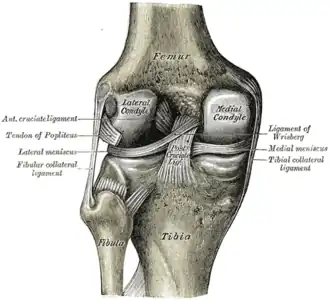

![]() Правый коленный сустав, сбоку. | |

![]() Левый коленный сустав сзади, показаны внутренние связки. | |

Коле́нный сустав, коле́но (лат. articulatio genus) — сустав, соединяющий бедренную кость, большеберцовую кость и надколенник. Является сложным (в образовании сустава участвуют три кости), комплексным (содержит мениски). По форме является мыщелковым.

В передней части сустава расположен надколенник (коленная чашечка). Надколенник и четырёхглавая мышца бедра соединены сухожилием, продолжением которого является связка надколенника. В связочный аппарат входят:

- боковые (малоберцовая и большеберцовая коллатеральные)

- задние (подколенная, дугообразная, связка надколенника, медиальная и латеральная поддерживающие)

- внутрисуставные (крестообразные, поперечная связка колена (между менисками)

Крестообразные связки находятся в полости коленного сустава. К разрывам их приводят запредельные движения в коленном суставе.

- Передняя крестообразная связка (лат. lig. cruciatum anterius) начинается от задневерхней части внутренней поверхности наружного мыщелка (костного выступа) бедренной кости, пересекает полость коленного сустава и прикрепляется к передней части межмыщелкового возвышения большеберцовой кости также в полости сустава. Эта связка стабилизирует коленный сустав и не даёт голени чрезмерно смещаться вперёд, а также удерживает наружный мыщелок большеберцовой кости.

- Задняя крестообразная связка коленного сустава (лат. lig. cruciatum posterius) начинается от передневерхней части боковой поверхности внутреннего мыщелка бедра, пересекает коленный сустав и прикрепляется к наружной части межмыщелкового возвышения большеберцовой кости. Она стабилизирует коленный сустав, и удерживает голень от смещения назад.

Суставные поверхности костей покрыты хрящом. Между сочленяющимися поверхностями бедренной и большеберцовой костей имеются внутренний и наружный мениски, представляющие собой серповидные (формы полулуний) хрящи. Коленный сустав имеет несколько синовиальных сумок:

Передний и латеральный вид колена.